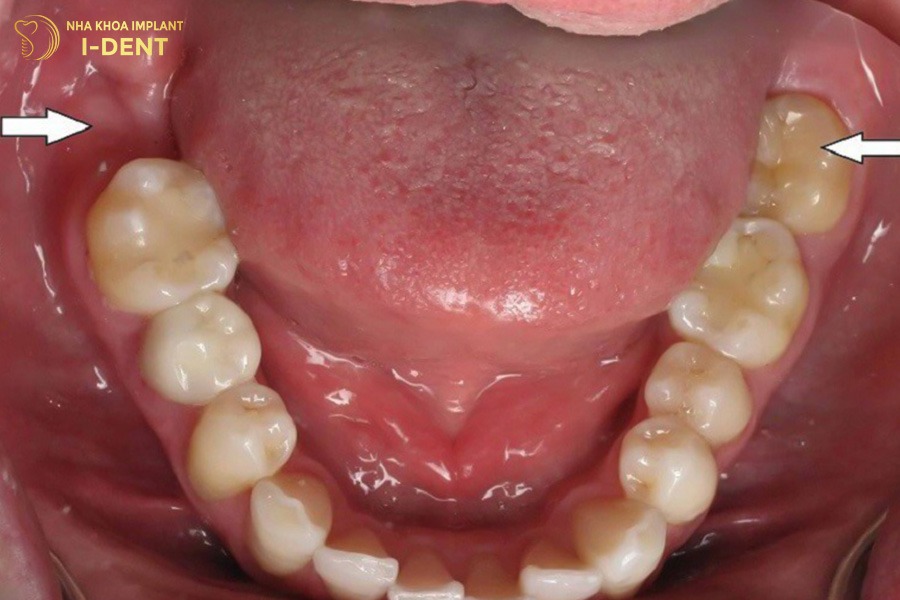

Vị trí của răng số 7

Răng số 7 nằm giữa răng số 6 và răng khôn trên cung hàm, thường mọc vĩnh viễn vào khoảng năm 12 tuổi và chỉ mọc duy nhất một lần trong đời. Điều này đồng nghĩa nếu bị mất răng số 7, chiếc răng này sẽ không thể tự mọc lại. Vì vậy, khi bị mất răng số 7 cần điều trị sớm để tránh ảnh hưởng đến chức năng ăn nhai và cấu trúc hàm về lâu dài.

Một người trưởng thành thường có 32 chiếc răng vĩnh viễn, được chia đều cho 2 hàm trên dưới, mỗi hàm 16 răng. Dựa vào hình dáng và chức năng, hệ thống răng được chia thành 4 nhóm là nhóm răng cửa, nhóm răng nanh, nhóm răng hàm nhỏ và nhóm răng hàm dưới. Trong đó nhóm răng hàm lớn có tổng 12 chiếc răng gồm 4 chiếc răng số 6, 4 chiếc răng số 7 và 4 răng khôn (răng số 8) mọc sau. Răng số 7 là răng hàm thứ 2, đóng vai trò rất quan trọng trong việc nghiền nhỏ thức ăn và duy trì lực nhai cân đối giữa 2 hàm. Nhờ có răng số 7, quá trình tiêu hóa diễn ra nhẹ nhàng, thuận lợi hơn.